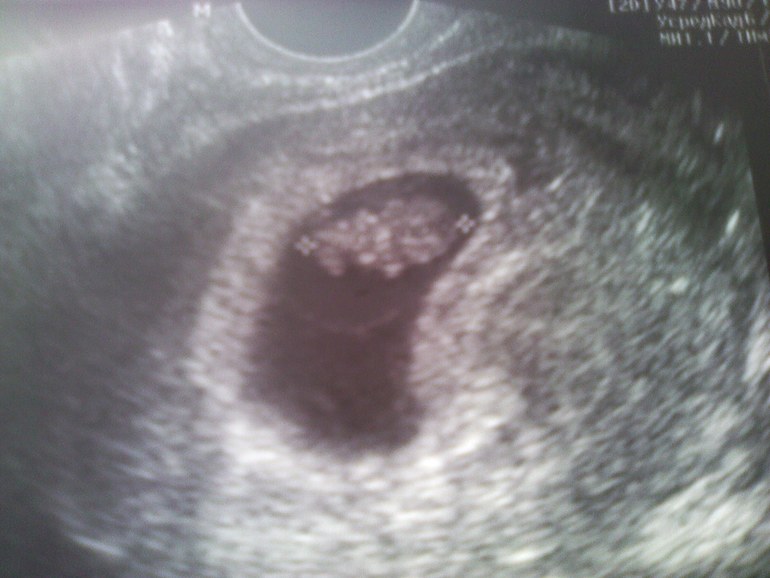

2-й,но окончательный пост!!!У НАС ПОЛУЧИЛООСЬ!!!

Спасиииибо огромное тебе!!!Про веру это так точно  сказано!!! super_smilies086.gifпрыгаю по дому хожу,танцую!!! in_love.gifТонусу мы конечно не очень то рады,но ничего,мы и с ним справимся!! music.gif

ААААА,я так об этом мечтаю!!!Сегодня после узи весь день мечтаю!!!Он прям совсем человечек уже!!!Пупсичек мой!!!!